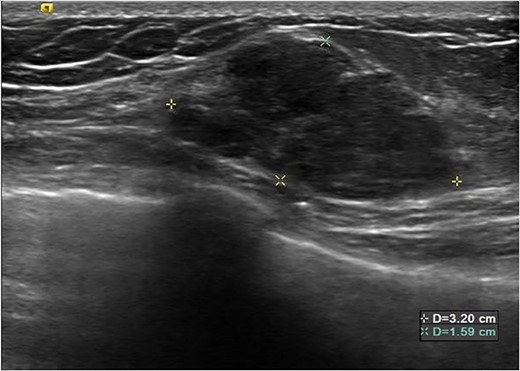

A 26-year-old female presented with a longstanding palpable fibroadenoma in the left breast. She was first investigated with ultrasound imaging showing a lobulated 2.4 × 2.5 × 1.4 cm hypoechoic lesion with well-defined margins (Fig. 1). She underwent core needle biopsy of the lesion which was histologically proven to be a fibroadenoma. There was no evidence of malignancy. She was later discharged and presented 6 years later with a history of recent enlargement of the left breast lump. Ultrasound imaging now showed increase in the size of the left breast fibroadenoma to 3.2 × 2.7 × 1.6 cm and development of an irregular outline (Fig. 2). Because of increasing size of the lesion and new indeterminate features, excision biopsy was advised. Post-excision histology revealed a 5-mm focus of classic lobular carcinoma in situ (LCIS) with a 0.6-mm area of microinvasive carcinoma within the fibroadenoma (Figs 3–6). The carcinoma was estrogen and progesterone receptor positive and Her2 negative. Atypical ductal hyperplasia was seen in the breast tissue adjoining the fibroadenoma. After presentation at our multidisciplinary tumor board, sentinel lymph node biopsy for staging of the invasive carcinoma, radiotherapy and endocrine therapy for risk and recurrence reduction, as well as genetic testing in view of her young age was discussed with the patient. Because of the small size of the invasive carcinoma, potential cost and morbidity associated with sentinel lymph node biopsy, no further surgery was performed. The patient was agreeable to proceed with radiotherapy and endocrine therapy but requested to defer genetic testing.

Subsequent ultrasound demonstrating increase in size of the left breast mass now measuring 3.2 × 2.7 × 1.6 cm. There was also new development of irregular margins, giving an indeterminate appearance.